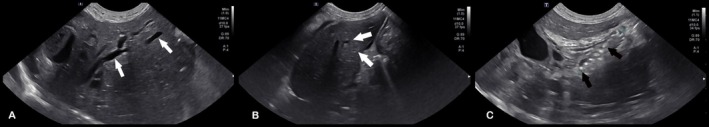

Post‐operative radiographs confirmed appropriate placement of the stent and the biliary drainage catheter (Figure 2). Abdominal ultrasonography showed asymmetric biliary tract decompression, with persistent right‐sided intrahepatic biliary tract dilatation (Figure 3A) and resolved left intrahepatic biliary tract dilatation (Figure 3B). The stent was visualized extending from the duodenal lumen through the CBD and into the left lateral liver lobe within the biliary tract (Figure 3C). A large volume of echogenic peritoneal effusion also was observed with hyperechoic mesenteric fat. Fluid analysis was consistent with mild mixed inflammation; no bacteria were seen; aerobic and anaerobic cultures were negative.